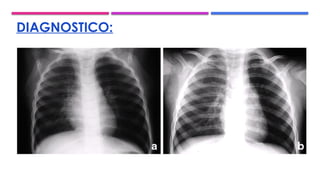

DIAGNOSTICO: